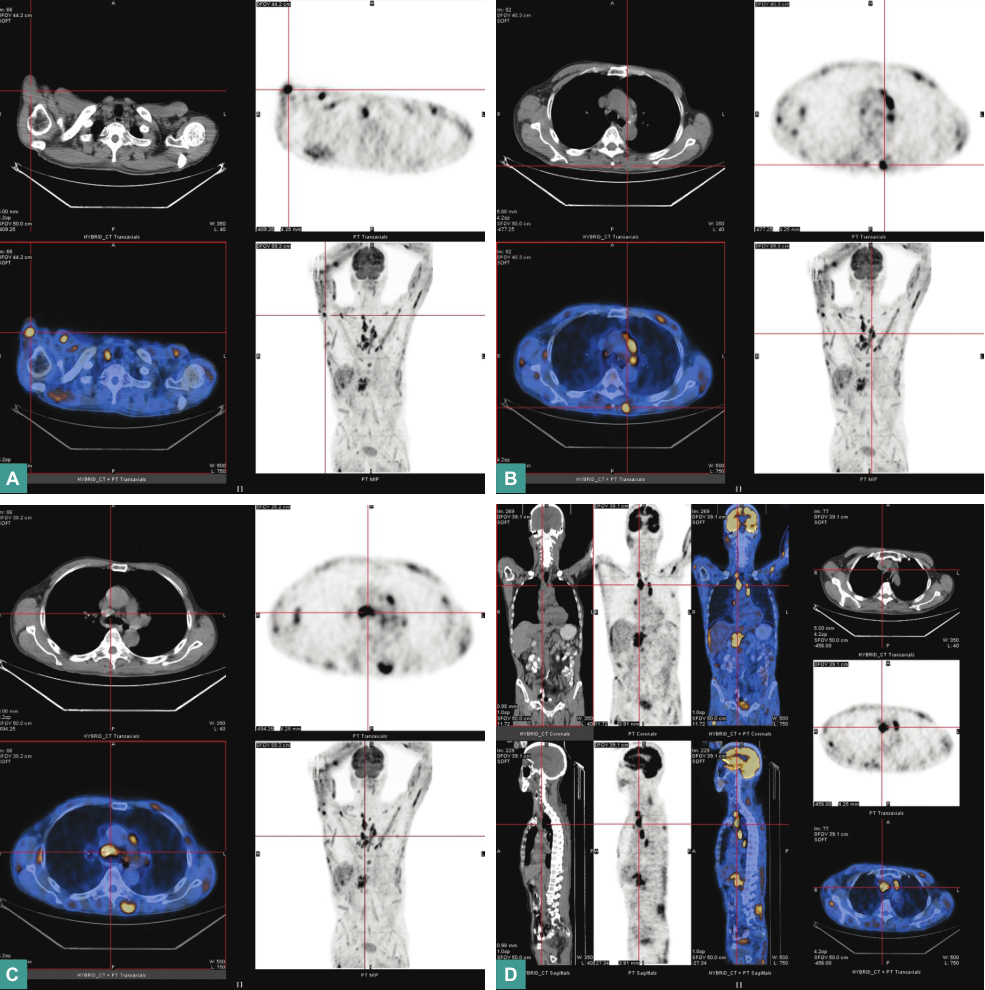

全身正电子发射计算机断层显像(positron emission tomography,PET)-CT(图1):

图1 全身PET-CT扫描

①全身肌肉多发高代谢灶,右侧锁骨上窝、纵隔内及腹膜后多发高代谢结节影;②右肺上叶后段及右肺中叶近胸膜下少许小结节影,代谢未见增高;③双肺散在多发斑片影、结节影、条索影,代谢未见增高;④肺气肿,双侧胸膜轻度增厚;⑤脾轻度增大;⑥双肾结石;前列腺钙化灶;⑦双侧颈部、腋窝、肝胃间隙及双侧腹股沟区多发小结节影,代谢未见增高。

全身PET-CT提示全身肌肉多发高代谢灶,右肺上叶、中叶近胸膜下小结节,考虑有炎性肉芽肿可能。

恶性肿瘤导致的高钙血症发生率仅次于甲状旁腺功能亢进症(甲旁亢),其中血液系统肿瘤约占20%。本例患者为老年男性,虽然各项肿瘤指标阴性,碱性磷酸酶(alkaline phosphatase,ALP)、乳酸脱氢酶(lactate dehydrogenase,LDH)等指标正常,但是PET-CT提示全身肌肉多发高代谢灶,右侧锁骨上窝、纵隔内及腹膜后多发高代谢结节影,为淋巴瘤可能性大,下一步可进行骨髓片检查、肌肉结节活检等进一步明确诊断。

本类疾病患者发生高血钙的概率为2%~12%。本例患者否认结核病史,无咳嗽、咳痰、咯血以及发热、消瘦等结核中毒症状,结核分枝杆菌感染相关指标阴性,不支持结核病诊断。但影像学检查提示的病变部位系结核好发部位(PET-CT提示右肺上叶后段及右肺中叶近胸膜下有少许小结节影,考虑有肉芽肿可能),因此不能完全排除结核等肉芽肿疾病。

本例患者无典型结核中毒症状,T-SPOT阴性,以高钙血症的全身症状为首发表现,临床症状及肺部影像学表现均不典型,极易误诊和漏诊。对于诊断不明、病灶不明的高钙血症患者,需警惕结核病可能,并注意与淋巴瘤、韦格纳肉芽肿及其他特殊感染和转移性肿瘤相鉴别。全身PET-CT是一种对寻找原发病灶极富意义的诊断工具。